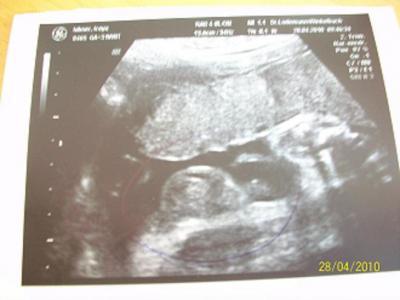

Somit keine SS Diabetis. Mein Mäuschen ist auch eine Woche kleiner als es sollte aber er sagte das es halt ein kleines, schmales Kind ist. Aber dann folgte der Schock. Aus unserer Prinzessin ist ein Prinz geworden. Es sah erst wieder alles nach nem Mädel aus, plötzlich sah ich einen Ball und mein Arzt auch. Nach 15 min Dauerschall konnten wir dann auch ein Foto bekommen. Tatsächlich ein Junge.

Das war es dann mit meiner Carlotta :( Jetzt suchen wir noch fleissig nach einem Jungennamen, das wäre ja ne Überraschung geworden im Kreisssaal.